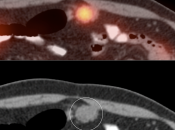

• Lesions less than 8.0 mm: These very small lesions (primary or metastatic) may have minimal or no appreciable uptake, as they are “beneath the resolution of PET”.

• Poorly-Avid Primary Subtypes:

• Mucinous carcinomas

• Signet ring cell carcinoma

• Poorly differentiated adenocarcinomas

• Small FDG-avid perigastric nodes can be masked by superimposed uptake from the primary lesion.